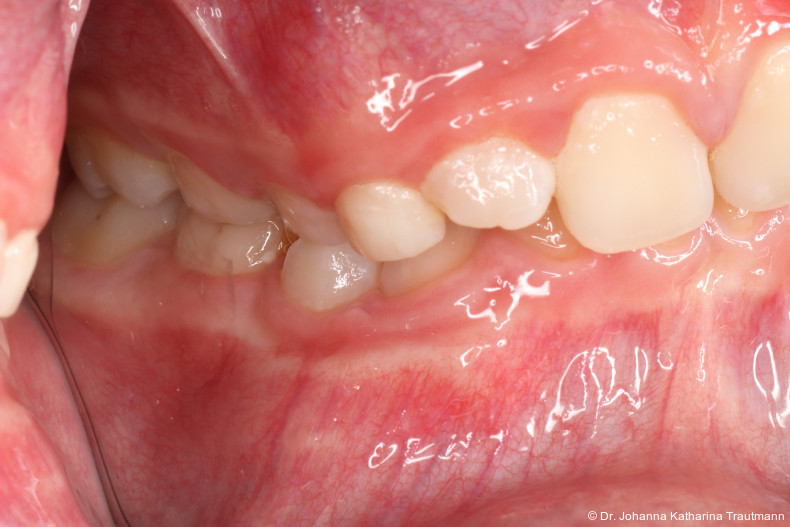

Das Fernröntgenseitenbild zeigte eine skelettale Klasse IIAnomalie mit einem Wits von 5,6 mm, bei einer tiefen Konfiguration (ML NL = 16,5°) mit bialveolär retrudierten Fronten (OK1NA = 5,9°; UK1NB = 10,4°), was sich auch in der Modellanalyse widerspiegelte. Hier zeigte sich zudem ein schmaler Oberkiefer mit multiplen Kippungen und Rotationen in der Front, einem hypoplastischem 22 sowie einer Mesialwanderung des 16. Des Weiteren zeigte sich eine asymmetrische Bisslage mit 1 PB distal rechts und ½ PB distal links bei einem Overjet von 2,5 mm sowie einem Overbite von 5 mm. Während im Unterkiefer bereits die zweite Zahnwechsel phase begonnen hatte, zeigte sich im Oberkiefer noch kein Wechsel in den Stützzonen. Gerade bei Patienten mit Spaltbildungen ist eine engmaschige Überwachung des Durchbruchs der oberen Eckzähne essenziell. Während bei der Allgemeinbevölkerung die Prävalenz von verlagerten Eckzähnen bei ca. 2,8 Prozent liegt2, ist diese bei Patienten mit Lippen-Kiefer-Gaumen-Spalten um den Faktor 10 erhöht.3, 4 Als klassische Risikofaktoren gelten zudem Platzmangel, transversale Enge aber auch Fehlstellungen, Nichtanlagen oder Hypoplasien der zweiten Schneidezähne. Diese übernehmen normalerweise die Funktion der Leitschiene für den S-förmigen Durchbruch der Eckzähne. Im vorliegenden Patientenfall kommen also mehrere Risikofaktoren für eine Verlagerung zusammen, was die rechtzeitige Diagnostik zur Abklärung einer Durchbruchsproblematik rechtfertigt. Da im Spaltbereich auch zusätzlich ein ausgeprägtes Knochendefizit vorliegen könnte, sollte auch immer die Option einer sekundären Osteoplastik abgewogen werden, deren Indikation und Timing optimal zum Durchbruch der Canini angepasst werden sollte.5

Das zunächst geplante Retentionskonzept aus herausnehmbarer und festsitzender Apparatur konnte leider nicht vollständig umgesetzt werden, da der Patient eine festsitzende Retention nicht wünschte. Die DVP ermöglichte zwar eine gute sagittale Retention, dennoch kam es zu einem Rezidiv der Zähne 33 und 43, die sich zum Behand lungsende mesiorotiert zeigten. Auch die Kongruenz der Mittellinien sowie die Korrektur der Torqueproblematik der Oberkiefereckzähne konnten nicht vollständig erreicht werden.